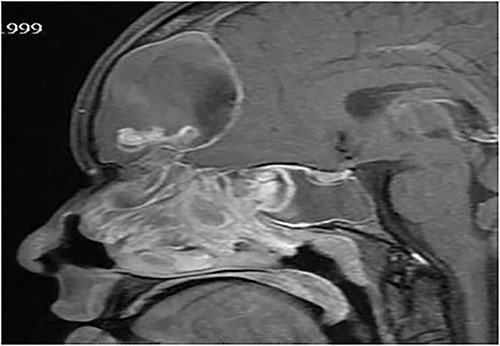

A 15-years-old male presented with bilateral nasal obstruction for a long time associated with nasal discharge, allergic nasal symptoms and headache. Endoscopic nasal examination revealed bilateral extensive nasal polyposis and mucin. CT scan (Fig. 7) and magnetic resonance imaging (MRI) scan (Fig. 8) of the paranasal sinuses confirmed the diagnosis of extensive bilateral allergic fungal pansinusitis with intraorbital and intracranial extradural extension. The patient underwent FESS, and all the polyps, mucin and fungal debris were removed from the sinuses. The patient continued on medical treatment and remained symptoms-free for 5 years follow-up.

Sagittal T1 post contrast MRI paranasal sinuses shows expansion of the frontal sinus and anterior ethmoid with intracranial extension limited by the dura. The sphenoid sinus shows complete opacification and expansion displacing the pituitary fossa superiorly. The nasal cavity is obliterated by nasal polyposis.